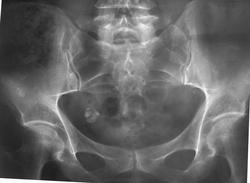

Здравствуйте. Сотрудница нашей клиники (50лет) проходит обследование в связи с генерализованной лимфаденопатией. На прямом снимке таза обращают внимание множественные участки остеосклероза в обеих подвздошных костях.

Как расценивать такие изменения?

проекцонно на область подвзошных костей могут накладываться постиньекционные оссификаты мягких тканей ягодичной области, пара дополнительных проекций могут помочь

Скорее всего не склероз, а остеопороз. Остальные участки обызвествлений это миома? и лимфоузлы.

Не увидела участков остеосклероза в подвздошных костях...

Да, наверно проекционно наложилось